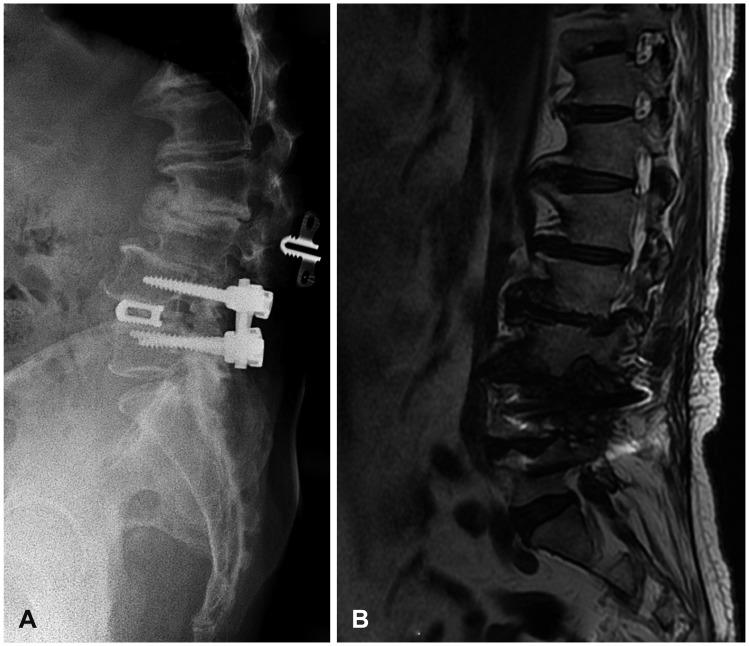

Lumbar fusion using the pedicle screw system is a popular operative procedure, with favorable clinical results and high fusion rates. However, the risk of adjacent segment disease after lumbar fusion is problematic. We report a complicated case of severe retrolisthesis at L3-4 level following dynamic interspinous process stabilization at L2-3 level and a fusion at L4-5 level. The radiological and clinical findings of this complication are discussed, and a review of the literature is presented.

使用椎弓根螺钉系统进行腰椎融合是一种常见的手术方法,临床效果良好且融合率高。然而,腰椎融合术后相邻节段疾病的风险是个问题。我们报告了一例复杂病例,在L2 - 3节段进行动态棘突间稳定术以及L4 - 5节段融合术后,L3 - 4节段出现严重的椎体后滑脱。本文讨论了该并发症的影像学和临床发现,并对相关文献进行了综述。